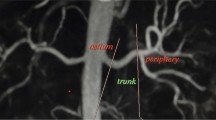

The readers noted the number of renal arteries. The overall quality of the imaging was graded on a 4-point scale from 1 (non-diagnostic images) to 4 (excellent image quality allowing optimal evaluation with high diagnostic confidence). The renal arteries were subjectively divided into four visible segments for analysis. The visible segments of the renal arteries (ostium, main, trunk and peripheral segments) (Fig. 1) were each graded on a 4-point scale from 1 (non-diagnostic images) to 4 (excellent image quality with high homogeneous signal intensity within the vessel lumen allowing optimal evaluation with high diagnostic confidence). Each renal artery segment (ostium, main, trunk, peripheral segments) was graded for stenosis as follows: (1) <20% luminal narrowing; (2) 20–49% luminal narrowing; (3) 50–74% luminal narrowing; (4) 75–99% luminal narrowing; (5) complete vessel occlusion with (1) to (2) being classified as haemodynamically insignificant renal artery stenosis (<50%) and (3) to (5) being considered as haemodynamically significant (≥50% stenosis), a criteria applied in previous studies [12, 13].

Our study is also limited since the division of the renal artery into four segments (Fig. 1) may be somewhat subjective, particularly between the main and trunk artery, leading to potential discrepancies in allocation of grading between segments: this limitation would tend to cause decreased sensitivity and specificity and may explain the slightly lower sensitivities when compared to other published data. This could potentially be addressed by grouping all segments together and considering each artery as a whole.